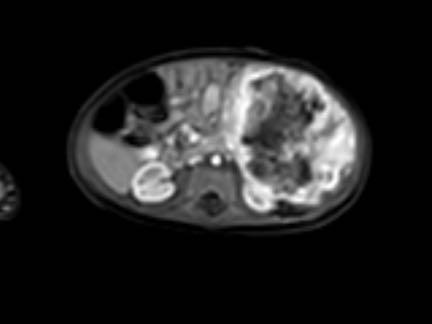

Mức độ lan rộng của khối u được đánh giá rõ ràng trên chuỗi xung TSE T2 weighted 3D theo mặt phẳng axial.

The left kidney is compressed and displaced caudally.

Có di căn hạch bạch huyết cạnh động mạch chủ (mũi tên vàng nhỏ).

Nguyên ủy của thân tạng và động mạch mạc treo tràng trên bị khối u bao quanh (đầu mũi tên).

Tĩnh mạch chủ dưới bị đẩy ra phía trước (mũi tên xanh).

Xẹp phổi hai bên ở vùng lưng thường được thấy trên MRI, vì việc kiểm tra được thực hiện dưới gây mê.